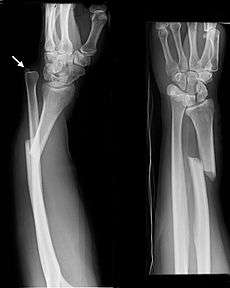

The Galeazzi fracture is a fracture of the radius with dislocation of the distal radioulnar joint. It classically involves an isolated fracture of the junction of the distal third and middle third of the radius with associated subluxation or dislocation of the distal radio-ulnar joint; the injury disrupts the forearm axis joint.[1]

Galeazzi fractures account for 3-7% of all forearm fractures. They are seen most often in males. Although Galeazzi fracture patterns are reportedly uncommon, they are estimated to account for 7% of all forearm fractures in adults.[1] They are associated with a fall on an outstretched arm.

The etiology of the Galeazzi fracture is thought to be a fall that causes an axial load to be placed on a hyperpronated forearm. However, researchers have been unable to reproduce the mechanism of injury in a laboratory setting.[1]